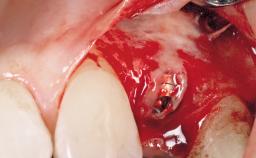

| Placement Protocol | Immediate implant placement |

| Socket Morphology | Single-root socket |

| Socket Integrity | Damage to one or more bone walls |

| Bone Volume | Damage to one or more socket walls |